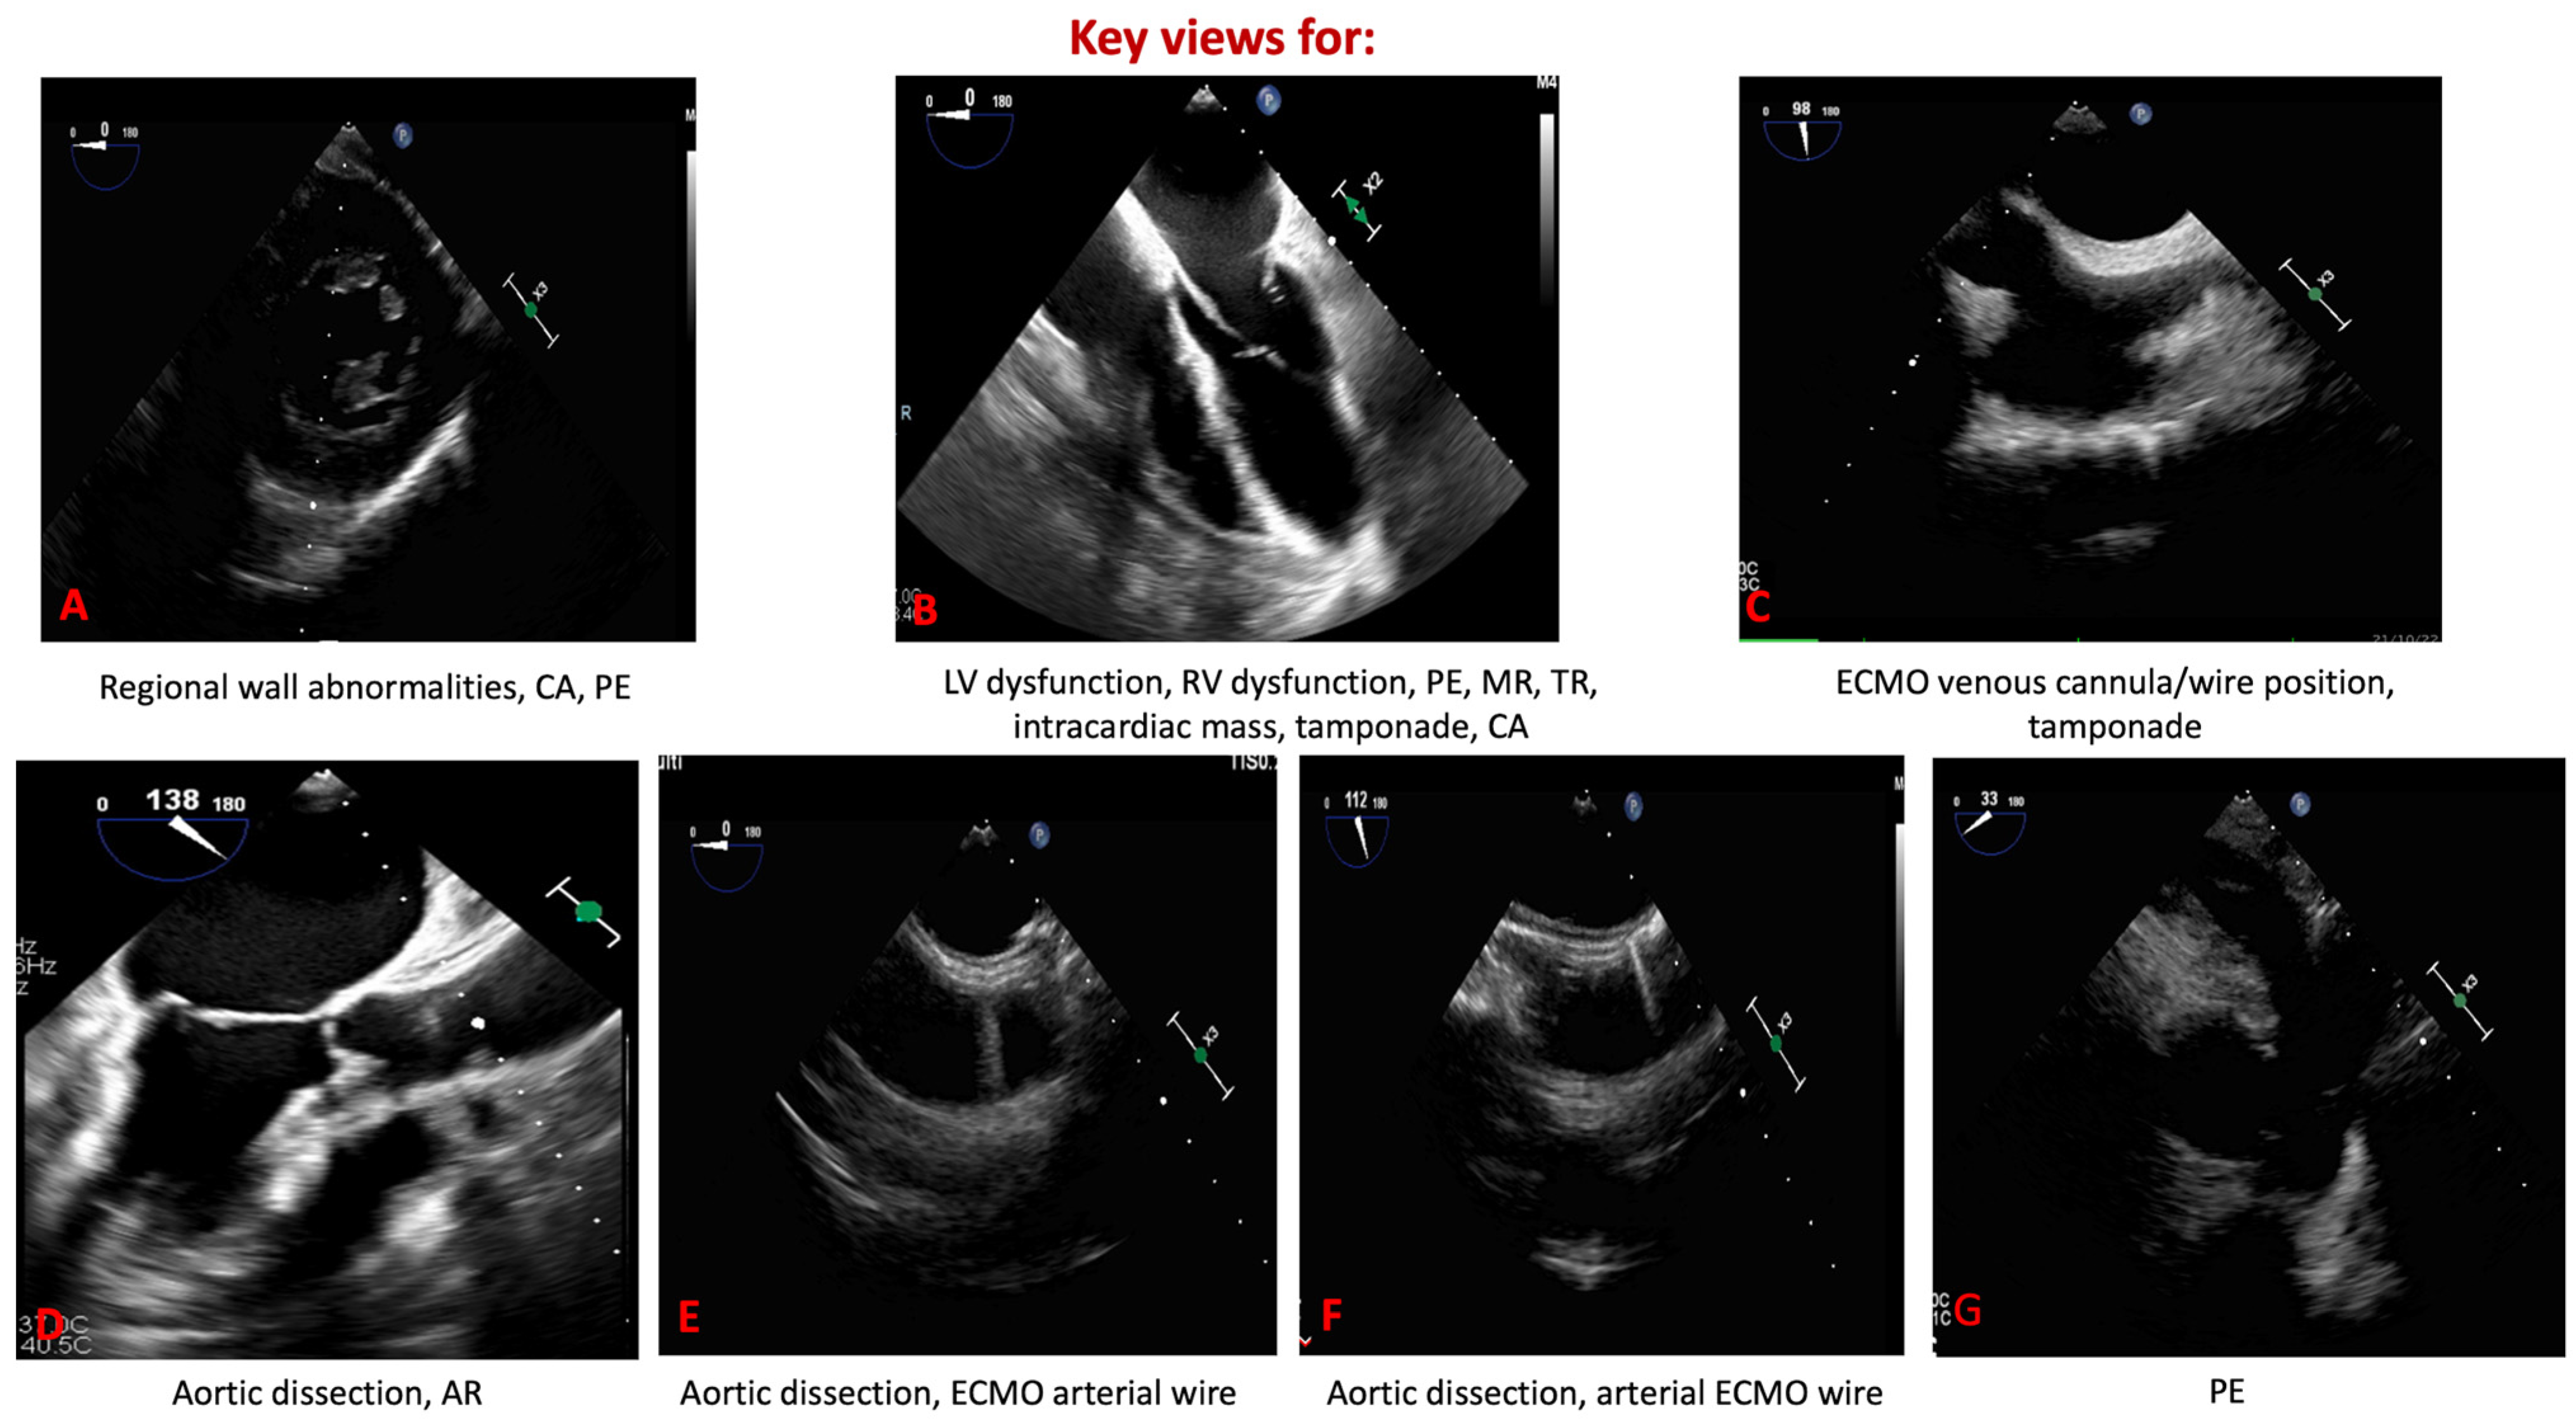

2. Materials and Methods

3. Relevant Sections

3.1. Introduction to the Physical Principles of Transesophageal Echocardiography

3.2. Clinical Advantages in the Critical Care and Emergency Setting

3.3. Reproducibility and Methodological Reliability of Quantitative TEE/TTE

3.4. The Role of TEE in Shock States

3.5. TEE in Pulmonary Embolism and Obstructive Shock

3.6. TEE in Cardiac Arrest

3.7. TEE in Cardiac Tamponade

3.8. TEE in ECMO Cannulation and Management

3.9. TEE in Aortic Dissection